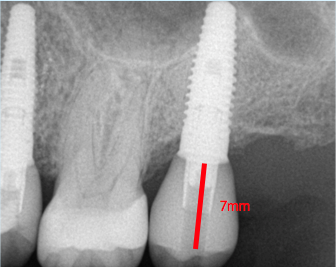

Fig. 1. Occlusal table to platform.

Figure 1

The author teaches "restorative address 73-422," a metaphorical street address, as the best method to help navigate an implant start to finish, where each number corresponds to a significant measurement. These measurements can be viewed by looking at the cross-section of a cone-beam computed tomography (CBCT) scan. The first number in the address, "7," represents the distance that the restorative platform should be from the desired occlusal table (Figure 1). An abutment 5 mm in length will minimize the chances of the restoration dislodging from the abutment. Then, above coronal to the abutment, there should be 2 mm of restorative material to ensure a strong restoration that will not fracture or break. Together, the abutment length of 5 mm plus the 2 mm of restorative material equals 7 mm. If the distance between the restorative platform of the implant abutment and the desired occlusal table is less than 7 mm, it will be difficult to mask out the screw-access hole and may result in an unsightly gray dot in the middle of the implant restoration (Figure 2). If the distance is slightly greater than 7 mm, that is acceptable, but it should not be less.